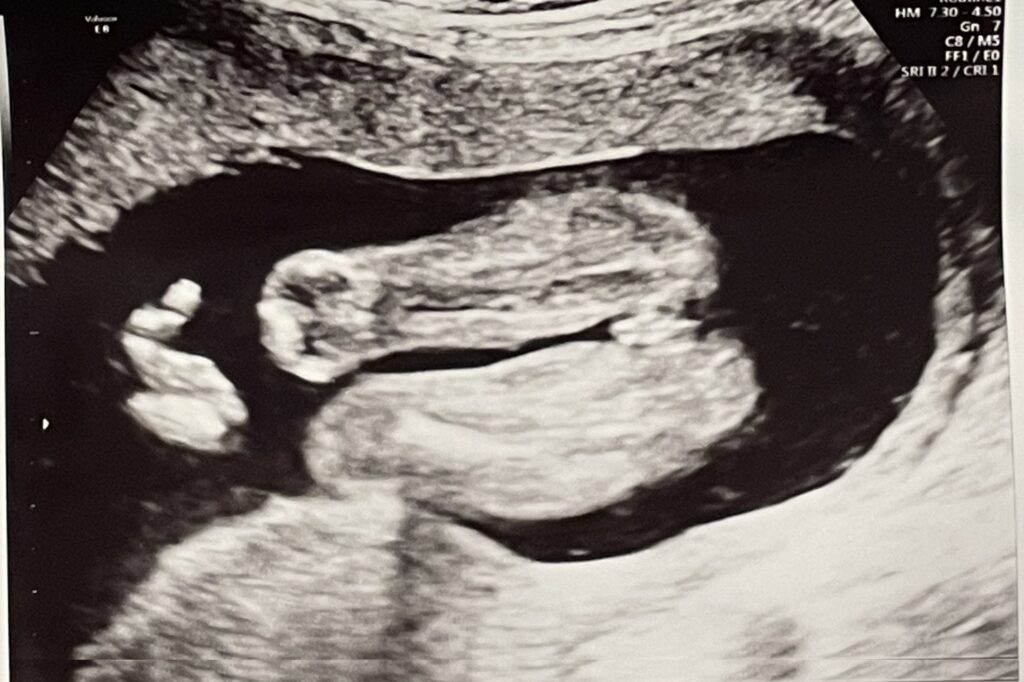

赤ちゃんの内臓や身体のパーツを拡大してチェックしたり、心臓がきちんと分かれているかなどを見たり、心音を聞いたり、色々なパーツのサイズをはかったりしていました。

先生のエコーでの検査が一通りおわった段階で、エコーをわたしに見せながらお顔や身体のパーツを見せてくれたり、心音を聞かせてくれたりしました。

胎動とエコーでの映像とで動いていることがリンクして、本当にお腹にいるんだなぁと思った瞬間でもあります。

女の子でした!女の子はおまたの間に、「コーヒー豆」や「木の葉マーク」と呼ばれる印が目印だそうです。

女の子と言われたけど生まれたら男の子だった!というのはたまに聞く話ですが、この日は体制もよかったためか先生によると「前も下もすっきりしているので、今のところは女の子だと思っていいですよ」とのことでした。